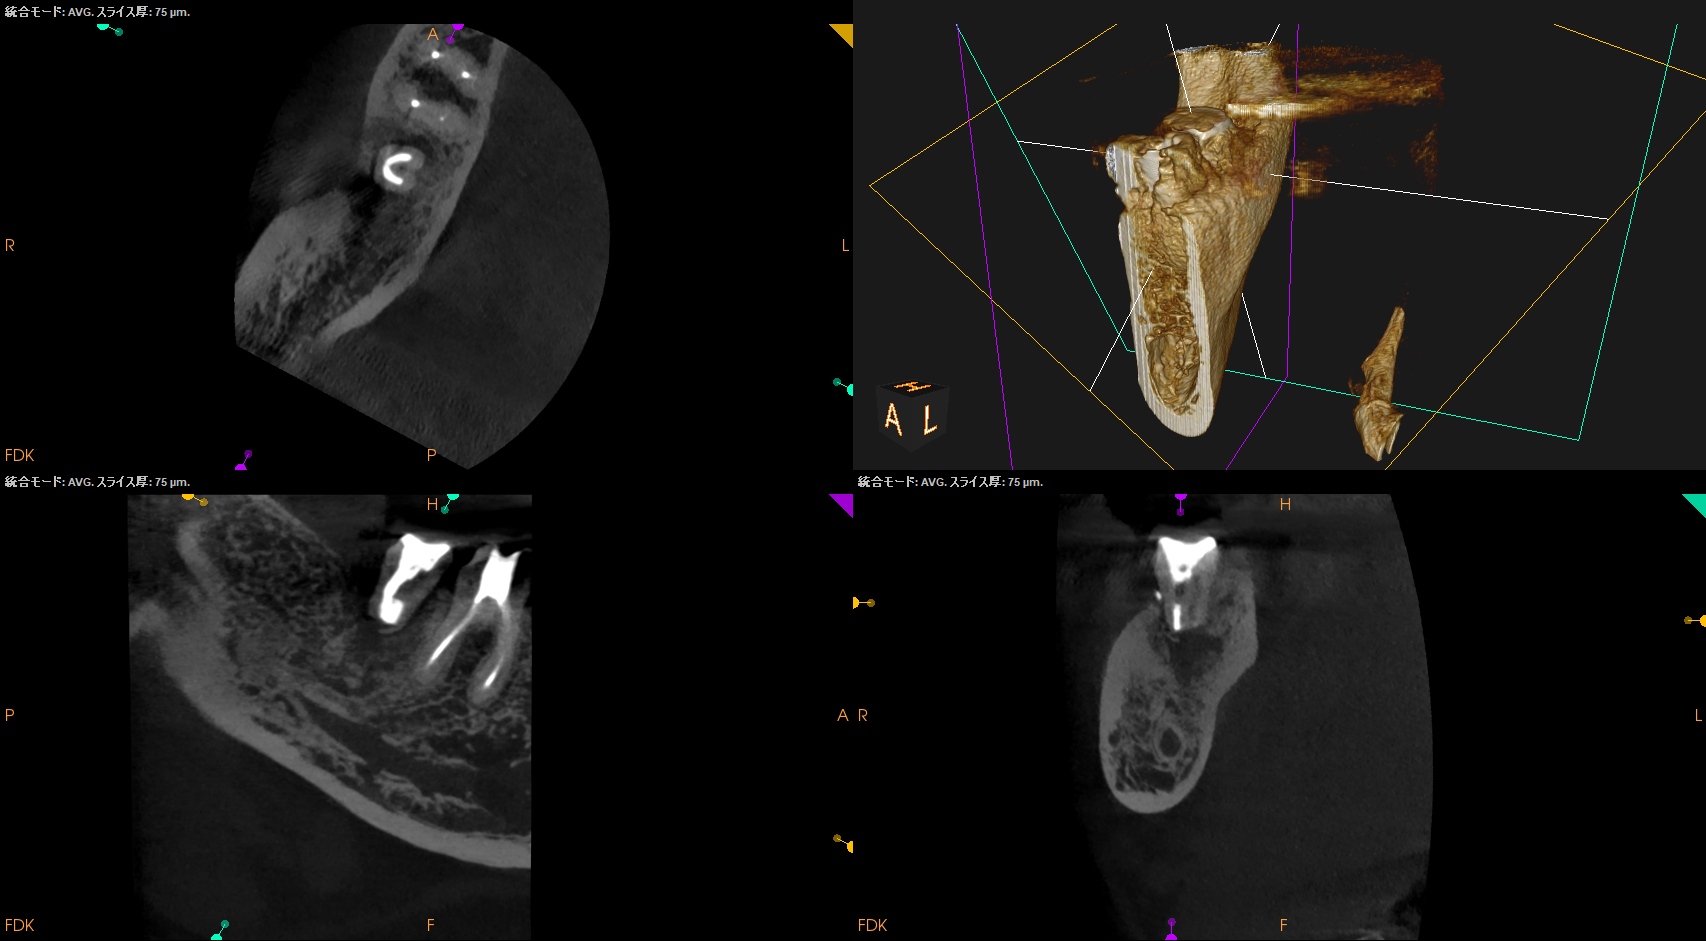

PA, CBCTを撮影した。

ML

MB

D

問題はないだろう。

この歯牙の根尖部の歯槽骨が回復するかどうか?は時間が解決する。

初診時と比較した。

初診時の絶望的な状況から改善されている。

最終補綴もOKと言えるだろう。

結論を言えばこの歯周ポケットはエンドが作ったものだったのだろう。

が、エンド病変が治癒したらそれが改善されている。

エンド→ペリオ病変であったと言うことだ。